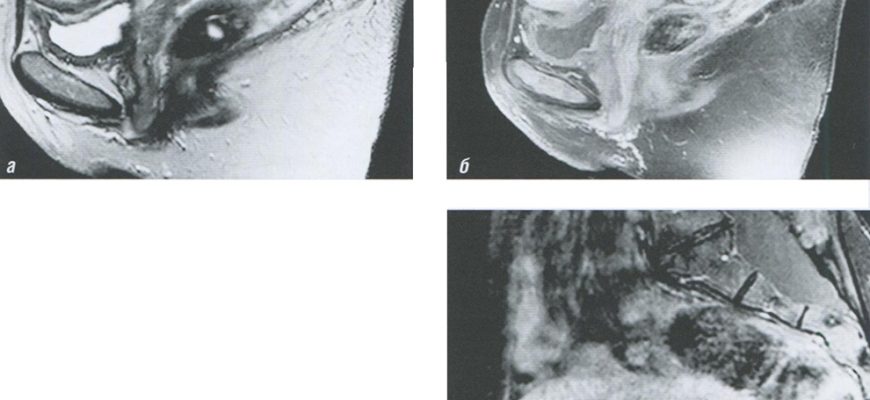

VR-моделирование работы МРТ-сканера: Шаг в будущее медицинской визуализации В мире медицины, где точность и детализация играют ключевую роль, новые технологии